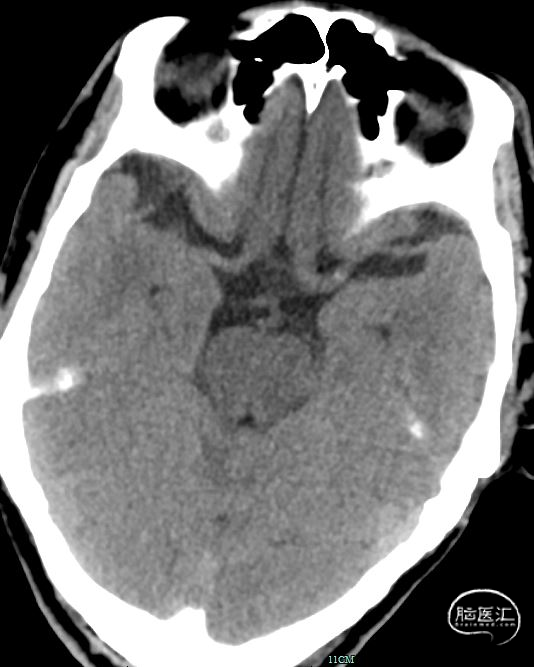

02、术前影像

为进一步评估梗死大小和颅内情况,磁共振显示颈内动脉闭塞,小的核心梗死。